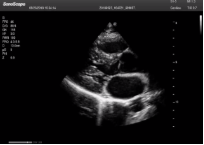

左室長軸

四腔心